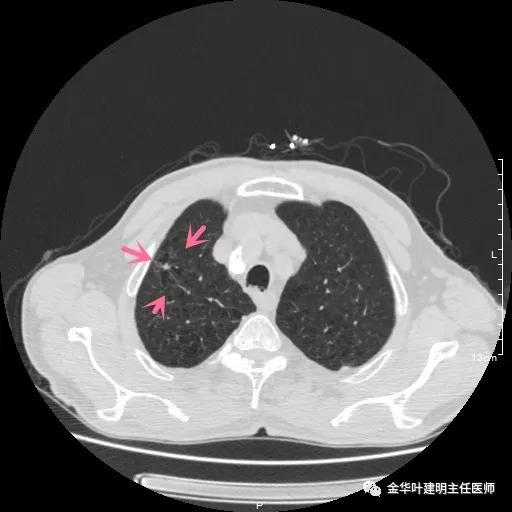

以上示右肺中叶病灶3。是混合磨玻璃结节,位置差,邻近肺门部,无法局部楔形切除,抗炎治疗后靶扫描显示了更清楚的细节,是典型的肺癌影像特征(此处未另提供)。从单病灶来看,需要行右肺中叶切除并清扫淋巴结才能得以治疗。